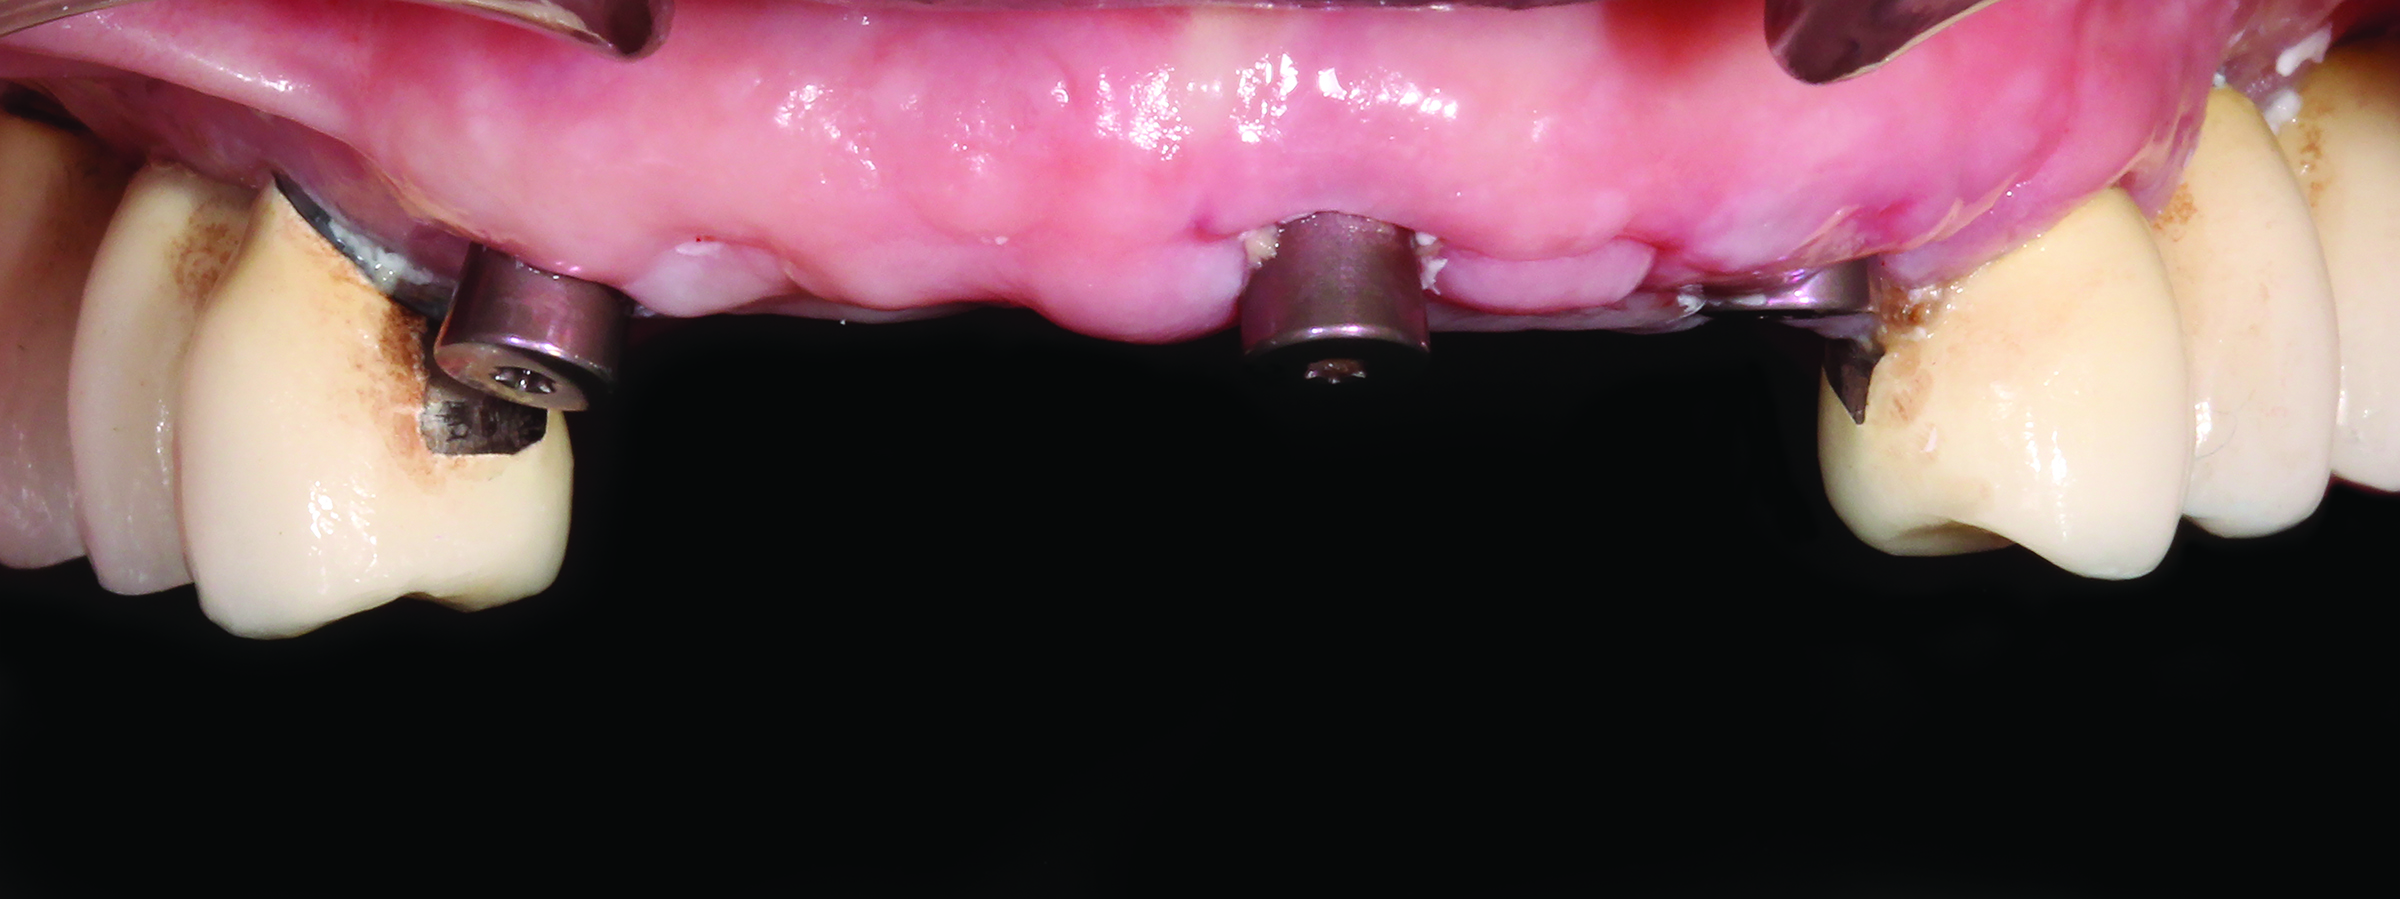

Fig 1. The patient’s initial presentation with healing abutments. (Surgical procedures performed by Mohammad Almogahwi, BDS, and prosthetic procedures performed by the author.)

Figure 1

Fig 2. Titanium screw-retained abutments are placed.

Figure 2